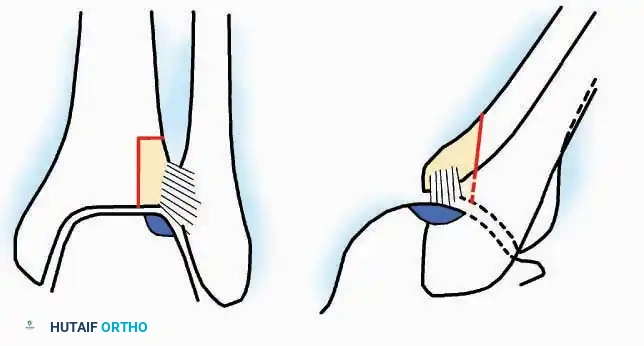

Medial Approach

Indications: Hallux valgus correction (bunionectomy), first MTP arthrodesis, or cheilectomy.

Surgical Technique:

* Incision: Make a curved incision 5 cm long on the medial aspect of the joint. Begin just proximal to the IP joint, curve it over the dorsum of the MTP joint (medial to the extensor hallucis longus [EHL] tendon), and terminate on the medial aspect of the first metatarsal 2.5 cm proximal to the joint.

* Superficial Dissection: As the deep fascia is incised, identify and laterally retract the medial branch of the first dorsal metatarsal artery and the medial branch of the dorsomedial nerve (a terminal branch of the superficial peroneal nerve).

* Deep Dissection: Dissect the fascia from the dorsum down to the bursa overlying the medial eminence of the metatarsal head.

* Capsulotomy: Make a curved incision through the bursa and joint capsule. Begin dorsomedially, continue proximally dorsal to the metatarsal head, sweep plantarward, and end distally on the medioplantar aspect of the joint. This creates an elliptical, racquet-shaped flap attached at the base of the proximal phalanx.

⚠️ Surgical Pitfall

While distal reflection of this racquet flap provides ample exposure of the first MTP joint, the extensive subfascial undermining required can compromise the vascularity of the skin flap, leading to delayed healing or necrosis. Consequently, the dorsomedial approach is often preferred in modern practice.

Dorsomedial Approach

Indications: Preferred approach for primary and revision first MTP arthroplasty, arthrodesis, and complex bunion corrections due to superior angiosome preservation.

Surgical Technique:

* Incision: Begin just proximal to the IP joint and extend proximally for 5 cm, running parallel and strictly medial to the EHL tendon.

* Exposure: Divide the superficial fascia. Identify and retract the EHL tendon laterally.

* Capsulotomy: The capsule can be incised longitudinally in the exact plane of the skin incision, allowing for subperiosteal elevation of the capsule medially and laterally, preserving the vascular supply to the medial skin flap.